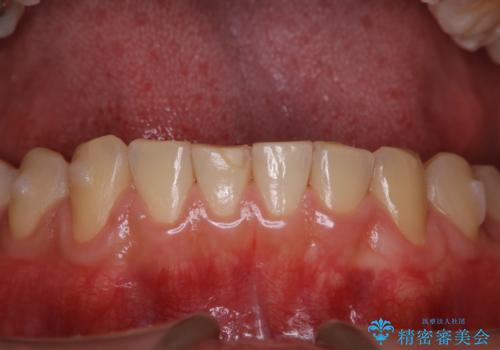

歯科医院にて染め出しをして歯磨き指導と専門的なクリーニング(PMTC)

- 久しぶりの来院のためクリーニング希望とのことでした。染め出しを行い、歯ブラシ指導とPMTC30分コースを行いました。

染め出し液を使ってプラークを染め出すことにより、普段の歯みがきで磨き残している場所を目で確かめることができます。

日々の歯磨きを上達するには、まずどこが磨けていないか認識することが大切です。